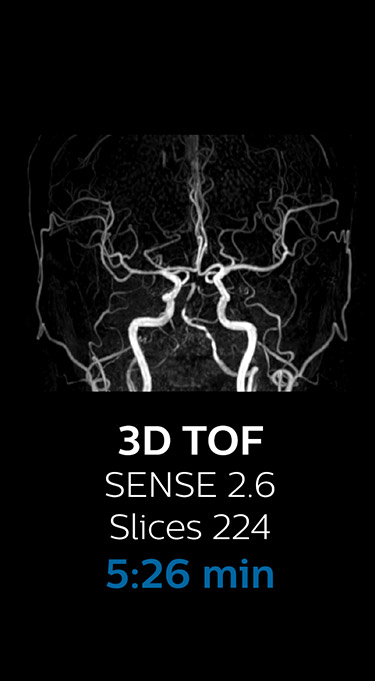

“We now only need about 10 minutes of scan time for a brain exam – and we still get the same amount of images and equal quality. We even managed to make a very useful improvement: we replaced the 43-second T21 FFE by a 43-second SWIp, which is more powerful for us in making confident diagnoses in certain patients.” “SWIp was not previously included in our standard protocol, because of its slightly longer scan time. SWIp provides high resolution 3D susceptibility weighted imaging in the brain, which helps to visualize small deoxygenated blood or calcium deposits. Now, with Compressed SENSE, we can perform 3D SWIp in only 43 seconds, so we have included SWIp instead of the 2D T21 FFE that we used previously. Without adding scan time, we now get SWIp images in every routine brain scan and it helps us increase our diagnostic confidence in certain cases.”

The most frequently used brain MRI examination at KNC included approximately 15 minutes of scanning time, and was quite comprehensive with fairly short scan times. When Compressed SENSE became available, its great impact on the brain exam quickly became clear.

Fast MRI of brain

With Compressed SENSE, the scan time for the routine brain examination at KNC was reduced from 15:48 to 10:19 minutes, which corresponds to 35% reduction.

Ingenia 3.0T CX

Scan time 15:48 min.

Brain with Compressed SENSE

Ingenia 3.0T CX

Scan time 10:19 min.